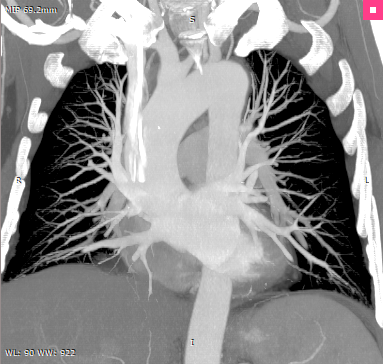

MIP |

•MIP (Maximum Intensity Projection)